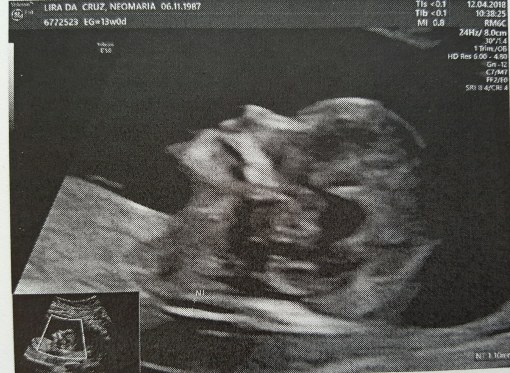

Agora que os três meses iniciais vulgo “de perigo” passaram, assim como os enjôos; agora que pude ver por duas vezes com meus próprios olhos que havia um outro ser dentro da minha barriga e pude ouvir seu coração bater aceleradamente; agora que através de vários exames me foi afirmado por diversas vezes que está tudo como deveria ser, posso comunicar oficialmente que seremos pais! Digo, eu já me considero mãe desde que vi o primeiro teste de farmácia resultar positivo, mas se for de acordo com o ditado “mãe/pai é quem cuida/cria”, então os títulos só poderão ser utilizados a partir do meio de outubro (o nascimento está estimado +- para o dia 18).

Não estou com pressa, nem tampouco querendo que o tempo pare, cada dia tem sido um dia especial, como todos deveriam ser. Tenho me cercado de boa literatura, de boa música, de muito amor, atenção e carinho. Acho que dentre os dias de maior exaltação emocional que tive desde a concepção, eu classificaria como o número 1 ver o resultado positivo do teste de farmácia, número 2 assistir ao primeiro ultra-som e número 3 o segundo ultra-som. É muito engraçado como nunca estou 100% convicta e segura do que acontece comigo, mas nessas 3 ocasiões por um breve momento tive esses estados de exaltação que nunca saberia colocar em palavras.